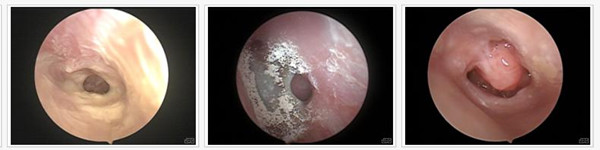

耳朵流脓各种耳类疾病的病历图

【精准诊断】领先设备--耳内窥镜精准诊断 对症治疗

西安中大耳鼻喉医院根据世界卫生组织诊疗规范标准,采用耳内窥镜诊断耳朵流脓的病因,采用冷光光源,亮度强,可将中耳、内耳结构放到500倍,导光性强、多角度,整个检查过程视野清晰,并配备闪光灯泡以及摄影内镜,可拍摄高清晰度的彩色照片。一目了然,便于医师更精准的观察病变组织,获取更加精准的病情发展,找准病因,从而制定针对性的治疗方案。